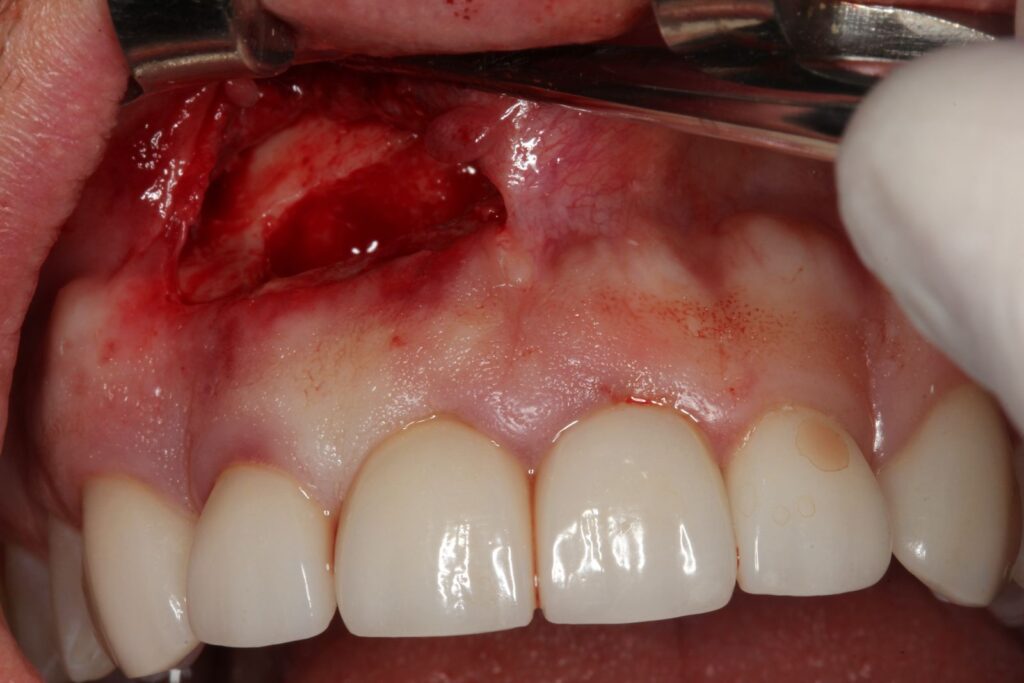

Apesar de ser um procedimento rápido, a apicectomia é realizada em ambiente cirúrgico, sob anestesia local, com todo o cuidado para garantir conforto e segurança ao paciente. O passo a passo do procedimento inclui:

Uma incisão na gengiva com bisturi, permitindo acesso à região óssea. A exposição da área infectada muitas vezes já revela a gravidade da lesão, seguida da drenagem do conteúdo infeccioso, quando presente.